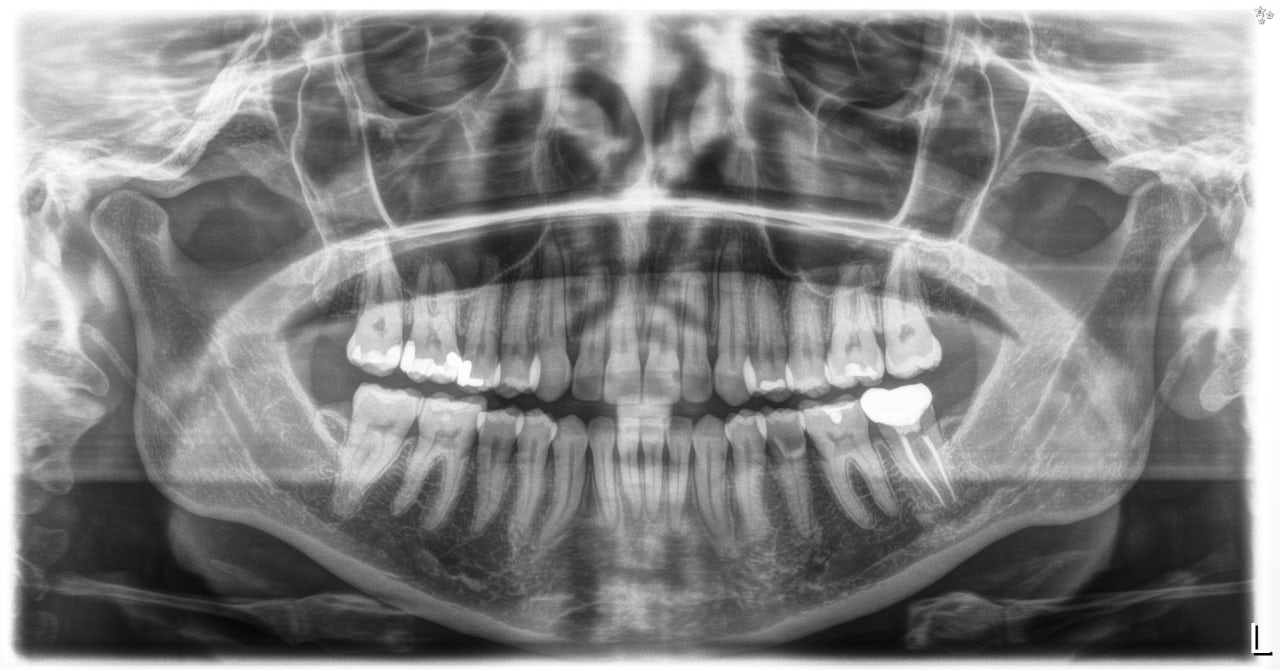

Case overview

Classification

Class I

Malocclusion

Crowding

Patient Information

Age: 43

Gender: Female

Chief complaint

Fix bottom middle crowding